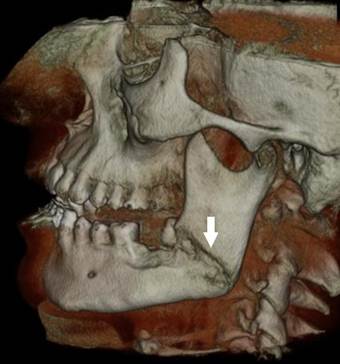

A 33-year-old male patient was referred to the Department of Oral Surgery, Faculty of Dentistry, Istanbul University, after an unsuccessful attempt to extract a partially erupted left third molar 1 week previously. The patient showed no significant disease or systemic condition. A panoramic radiograph and a volumetric tomographic scan showed an oblique and unfavorable fracture line on the left mandible that extended from the tooth roots to the mandibular angle (Figs. 4, 5).

Postoperative cone-beam computed tomography image of the patient showing the fracture line.